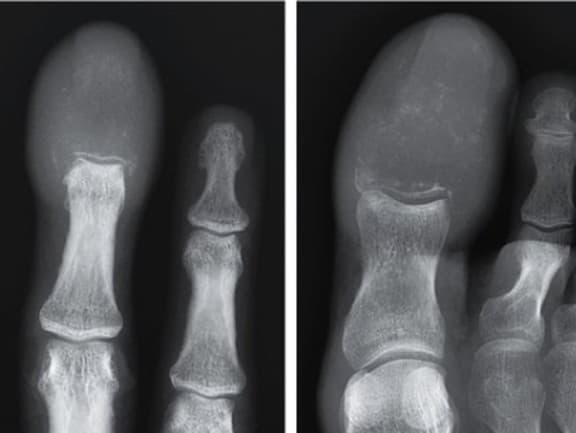

Lekári najskôr predpokladali, že ide o zápal, infekciu alebo dnu, no röntgenové snímky odhalili šokujúcu pravdu (Zdroj: X/@drkeithsiau)

Lekári najskôr predpokladali, že ide o zápal, infekciu alebo dnu, no röntgenové snímky odhalili šokujúcu pravdu. Kosti v oboch postihnutých končatinách boli doslova zničené a namiesto nich sa nachádzala len masa zhubného nádoru. Podľa správy publikovanej v prestížnom časopise The New England Journal of Medicine muž trpel metastatickým spinocelulárnym karcinómom pľúc, informoval New York Post.

Počas šiestich týždňov sa u neho objavilo bolestivé opuchnutie pravého prostredníka a pravého palca na nohe. Prsty boli začervenané, stvrdnuté a citlivé na dotyk. Na palci sa navyše vytvoril vred pod nechtom. Až podrobné vyšetrenia ukázali, že ide o extrémne vzácny stav známy ako akrometastáza – teda metastatické postihnutie kostí prstov na rukách alebo nohách. Tento typ metastáz tvorí iba približne 0,1 % všetkých kostných metastáz a najčastejšie sa vyskytuje pri pokročilých štádiách rakoviny pľúc, tráviaceho traktu alebo močovo-pohlavného systému.